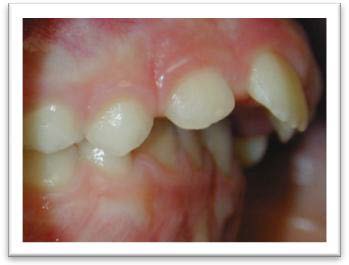

Risque de fractures des incisives supérieures quand elles sont trop avancées

Inversé articulé unilatéral qui peut entraîner une asymétrie osseuse et musculaire